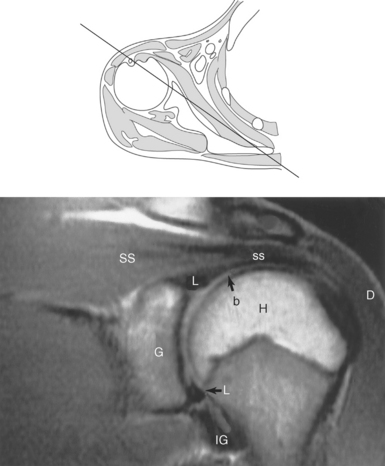

Figure 9.10 Sagittal oblique, T1-weighted MR scan of shoulder.

Key: cor, Coracoid process; cl, clavicle; sup, supraspinatus; ac, acromion; inf, infraspinatus; de, deltoid; tm, teres minor; gl, glenoid; sub, subscapularis; h, humerus; grt, greater tubercle; sc, scapula; glf, glenoid fossa; hh, humeral head.

The edge of the glenoid fossa is surrounded by a fibrocartilaginous ring termed the glenoid labrum (glenoid lip) (Figure 9.17). The glenoid labrum is a fold of the articular capsule, which functions to deepen the articular surface of the glenoid fossa. Superiorly, the labrum blends with the long head of the biceps brachii muscle. In cross section it appears triangular (Figure 9.18). The three glenohumeral ligaments (superior middle, and inferior) are thickenings of the fibrous capsule that surrounds the shoulder joint; they contributes to the formation of the glenoid labrum (Figures 9.17 and 9.19). They extend from the supraglenoid tubercle of the scapula to the lesser tubercle of the humerus. Also aiding in strengthening the fibrous capsule is the coracohumeral ligament that passes from the lateral side of the coracoid process of the scapula to the anatomic neck of the humerus (Figure 9.19). The coracoacromial ligament is another important ligament located on the anterior portion of the shoulder. As this ligament joins the coracoid process and acromion, it forms a strong bridge, termed the coracoacromial arch, which protects the humeral head and rotator cuff tendons from direct trauma and prevents displacement of the humeral head superiorly (Figures 9.17 and 9.19). The coracoclavicular ligaments help to maintain the position of the clavicle, in relation to the acromion, by spanning the distance between the clavicle and coracoid process of the scapula (Figure 9.19). The acromioclavicular ligament, at the acromioclavicular joint, provides support for the superior surface of the shoulder (Figures 9.17 and 9.19). The transverse humeral ligament is a broad band of connective tissue passing from the greater tubercle to the lesser tubercle of the humerus, forming a bridge over the intertubercular groove for protection of the long head of the biceps tendon (Figure 9.19). The ligaments of the shoulder are demonstrated in Figures 9.20 through 9.30.

Figure 9.27 Axial, T1-weighted MR scan of shoulder.

Key: c, Clavicle; cc, coracoclavicular ligament; CP, coracoid process; ch, coracohumeral ligament; D, deltoid muscle; H, humeral head; SB, subscapularis muscle; SS, supraspinatus muscle; G, glenoid fossa; L, labrum; ss, supraspinatus tendon; b, tendon of long head of biceps muscle; IG, inferior glenohumeral ligament; mg, middle glenohumeral ligament; sb, subscapularis tendon; T, teres minor muscle.